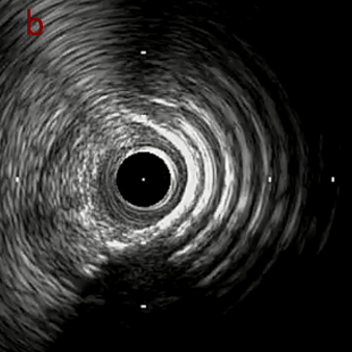

IVUS imaging

IVUSでは8時方向からPD枝がはいいてくる。

PreのIVUSではaの部位のみlipid plaqueを認め削ることでdistal embolismのリスクがあり、そのほかは270度の偏心性石灰化であるがwire biasは良好。